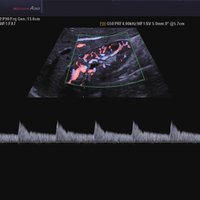

• Farb-Doppler

• Pulsed Wave (PW)-Spektral-Doppler

• Continuous Wave (CW)-Doppler

• Power-Doppler (PD)

• Directional Power Doppler (DPD)